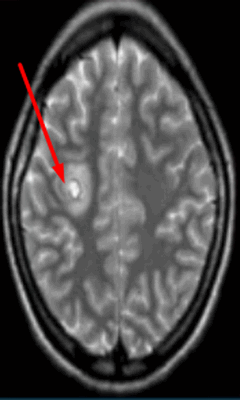

![Опухоль головного мозга на МРТ]()

Опухоль головного мозга на МРТ (указана стрелкой)